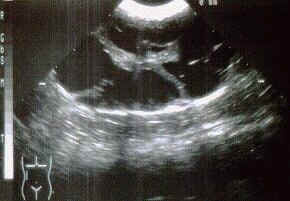

PKD ist das Ergebnis eines "autosomal dominanten" Gens und es ist daher relativ einfach aufzuspüren und auszuschließen. Alle zur Zucht verwendeten Katzen sollten mit Ultraschall untersucht werden um vorhandene Nierenzysten zu erkennen. Es dauert nur einige Minuten mit keiner oder einer kleinen Narkose. Wenn ein positives Ergebnis vorliegt und es möglich ist, dann lassen Sie die Elterntiere testen. Der einfachste Weg diese Krankheit auszuschließen, ist die positiven Tiere zu kastrieren. Wenn ein Zuchttier besonders wertvoll ist, dann ist es möglich PKD-negative Kitten zu bekommen, WENN das eine Elternteil PKD-negativ ist und WENN das positive Elternteil heterozygous ist. (Ist das positive Elternteil homozygous werden NUR positive Jungtiere fallen!!) Wenn die Kitten alt genug sind kann man Sie auf PKD testen lassen. Auf diesem Weg kann man sich seine Blutlinie erhalten und das betreffende positive Elternteil kastrieren. Es ist wahrscheinlich das viel mehr Perser von PKD betroffen sind als zur Zeit diagnostiziert wird. Mit mehr Studien und veröffentlichten Information über diese Krankheit können Züchter und Tierärzte daran arbeiten PKD-freie Zuchtprogramme zu erstellen. Auf diese Weise kann dieses genetische Gesundheitsproblem ausgeschlossen werden.